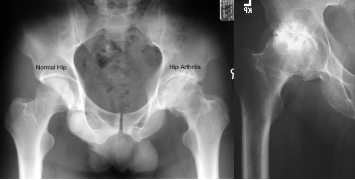

Diagnoza: Vendoset nëpërmjet ekzaminimit klinik, ku mjeku vlerëson shkallën e lëvizjeve të artikulacionit koksofemoral, dhe konfirmohet me anë të radiografisë. Radiografitë duhet të kryhen me ngarkesë (në këmbë), dhe në dy projeksione (anteroposterior dhe aksial). Ndonjëherë mund të jetë e dobishme një tomografi aksiale e kompjuterizuar (CT-Skaner).